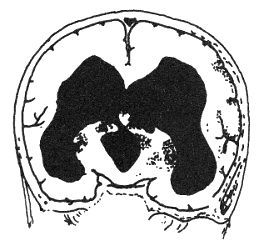

患兒腦室系統擴張,頭顱增大。腦室周圍白質水腫,甚至腦組織萎縮。側腦室壁可形成憩室或囊腫,其大小不一,若增大時可穿破大腦皮層,進入蛛網膜下腔,便形成CSF內引流,使腦積水可能靜止或形成腦外積水。

(四)CT掃描交通性腦積水時,腦室系統和枕大池均擴大;若有導水管狹窄,則僅側腦室和第三腦室擴大,而第四腦室正常。